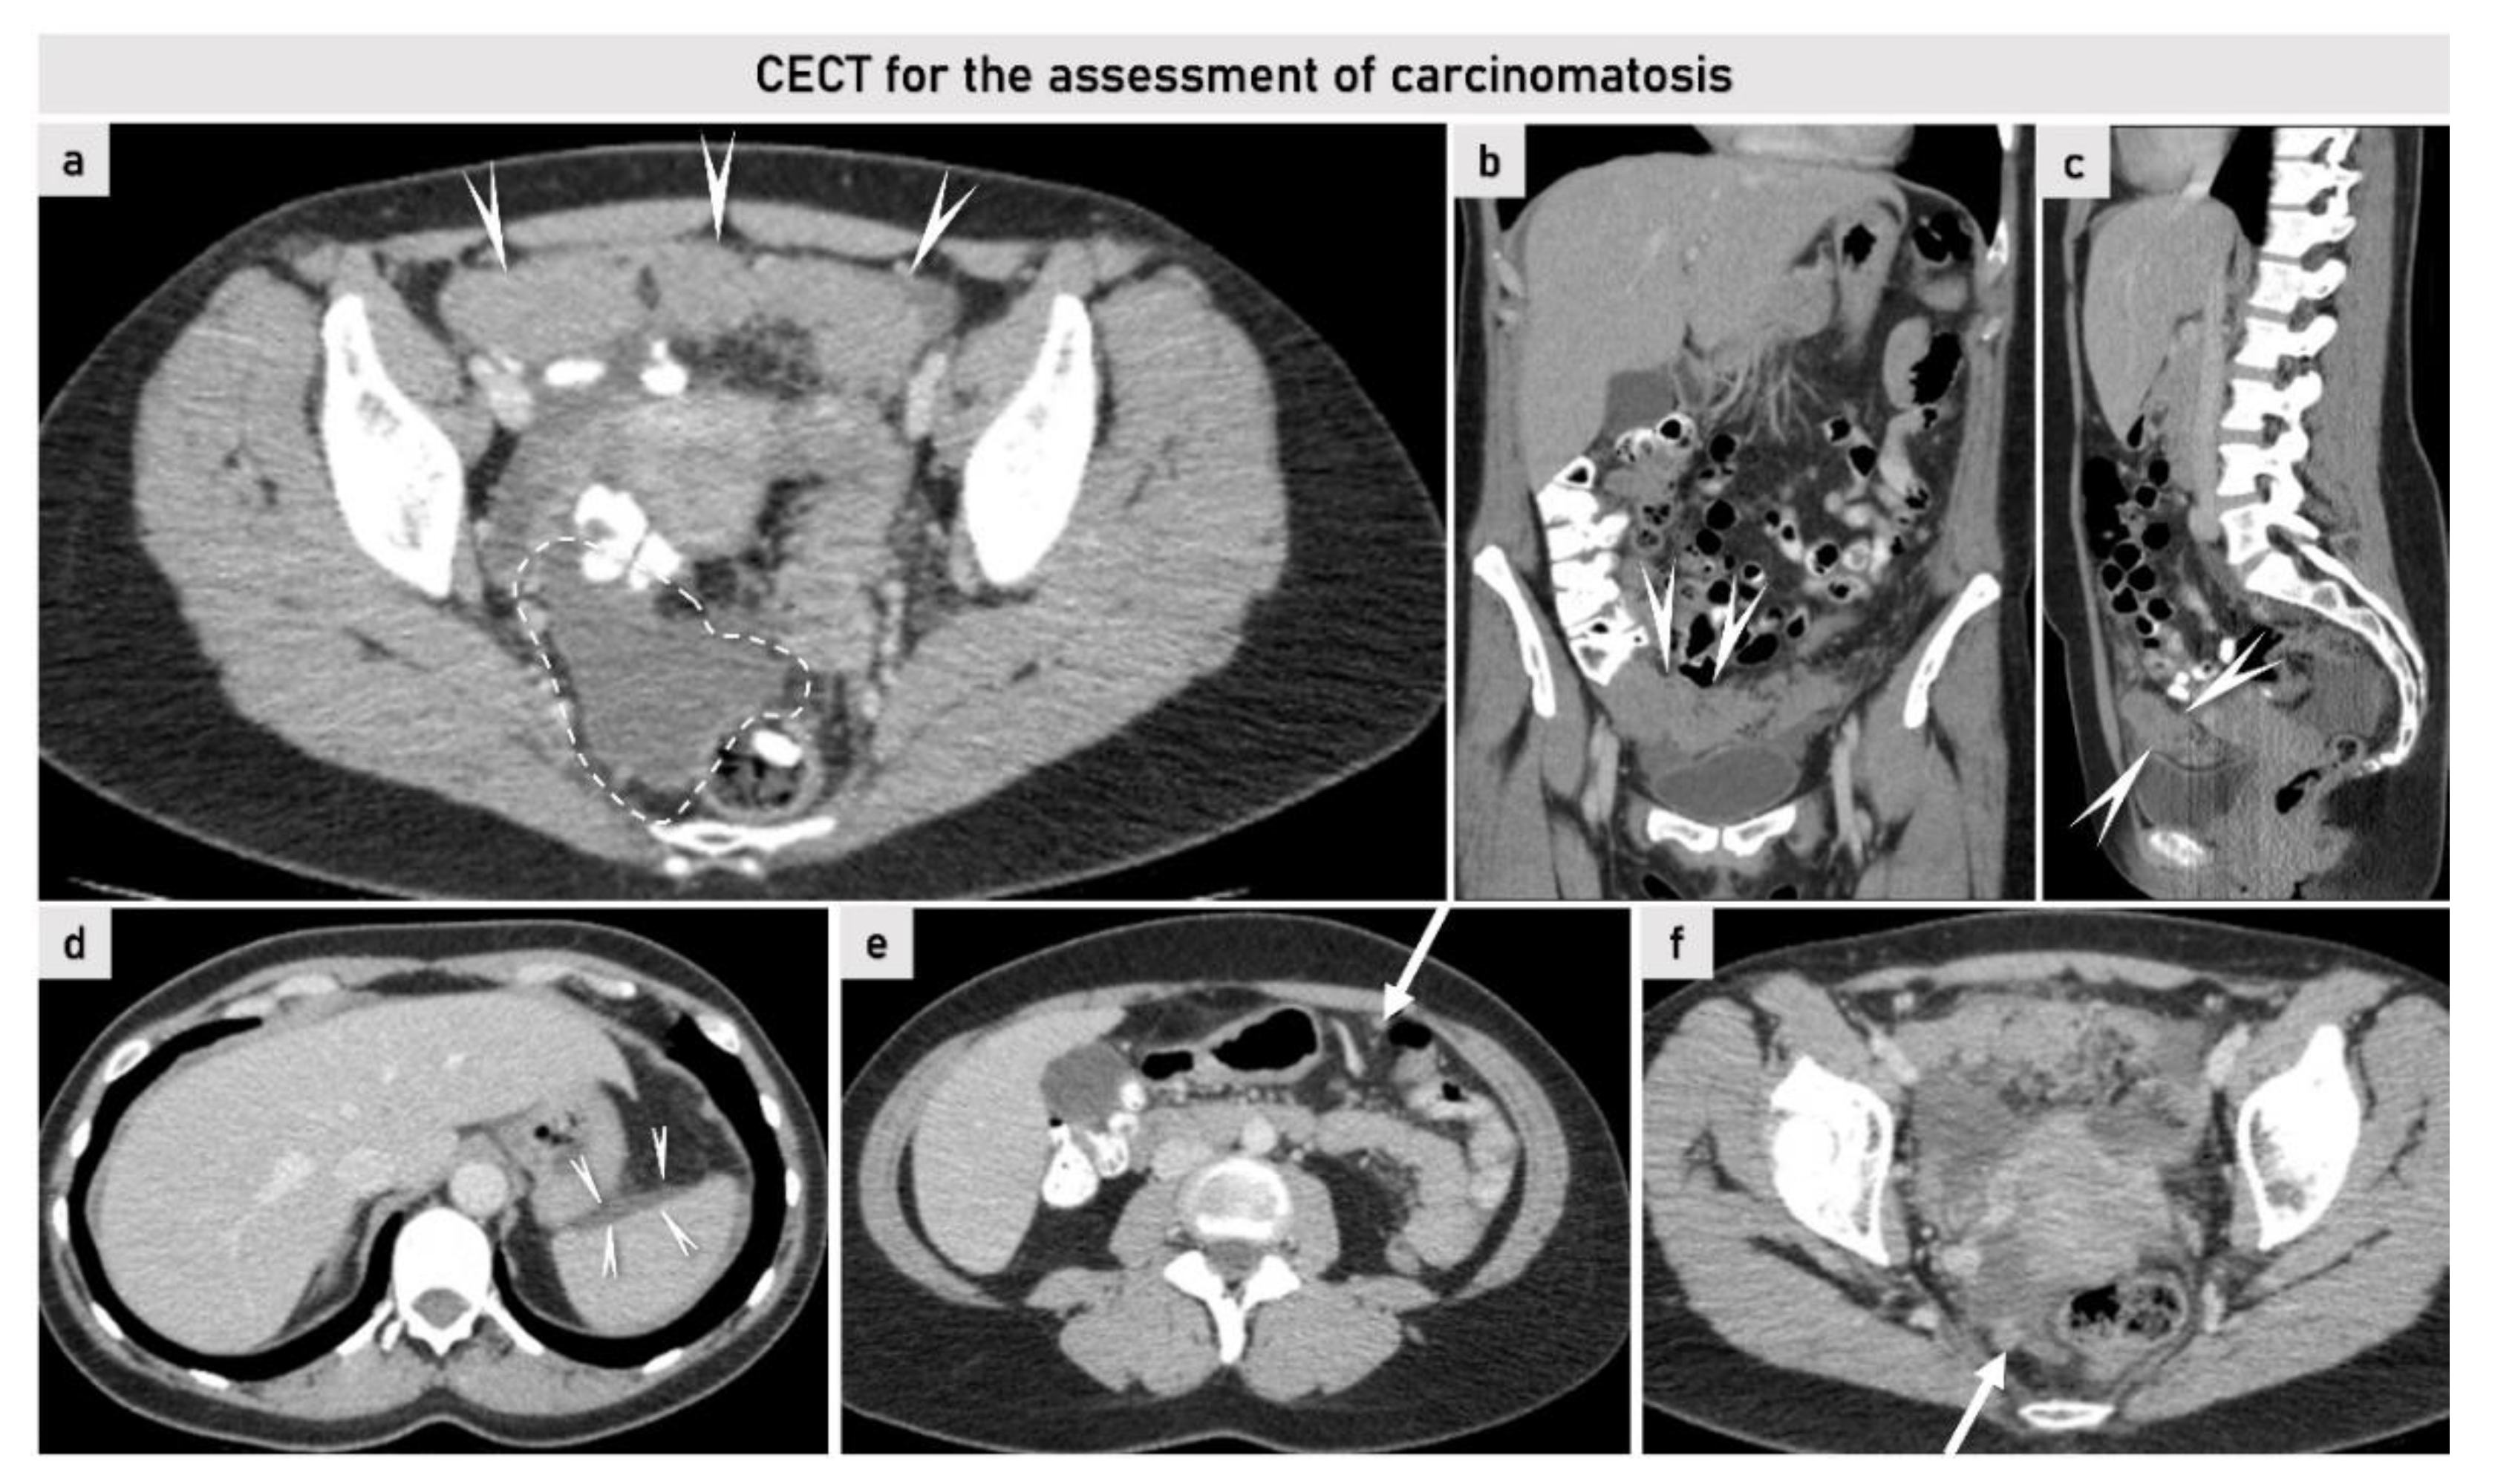

2.3.2. Computed Tomography

2.3.3. Magnetic Resonance Imaging